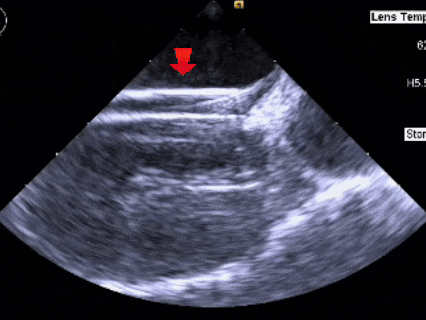

术中复测

测量膨出瘤基底宽19.61mm,深7.00mm

房间隔总长44.22mm,缺损大小14.80mm

超声可见房间隔连续中断,彩色多普勒可见过隔血流